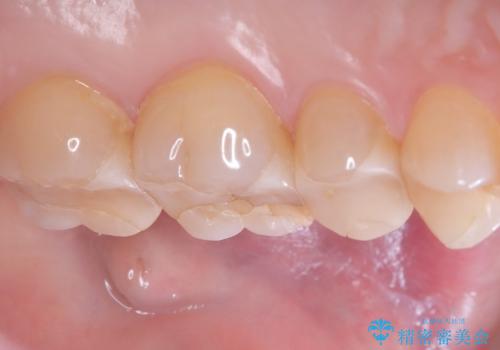

- 主訴:詰め物が欠けてしまった。

歯冠色インレーが一部欠けてしまい、他院にて部分的に樹脂のコーティング剤を付けてもらっている状態でした。

欠けている大きさが大きかったため、やり替えを提案しセラミックインレーでのやり替えとなりました。

他院にてセットしたセラミックインレーの一部が研磨では対応できない程大きく欠けてしまっていたため、やり替えとなりました。再度欠けぬよう、歯質を削り厚みを確保しています。